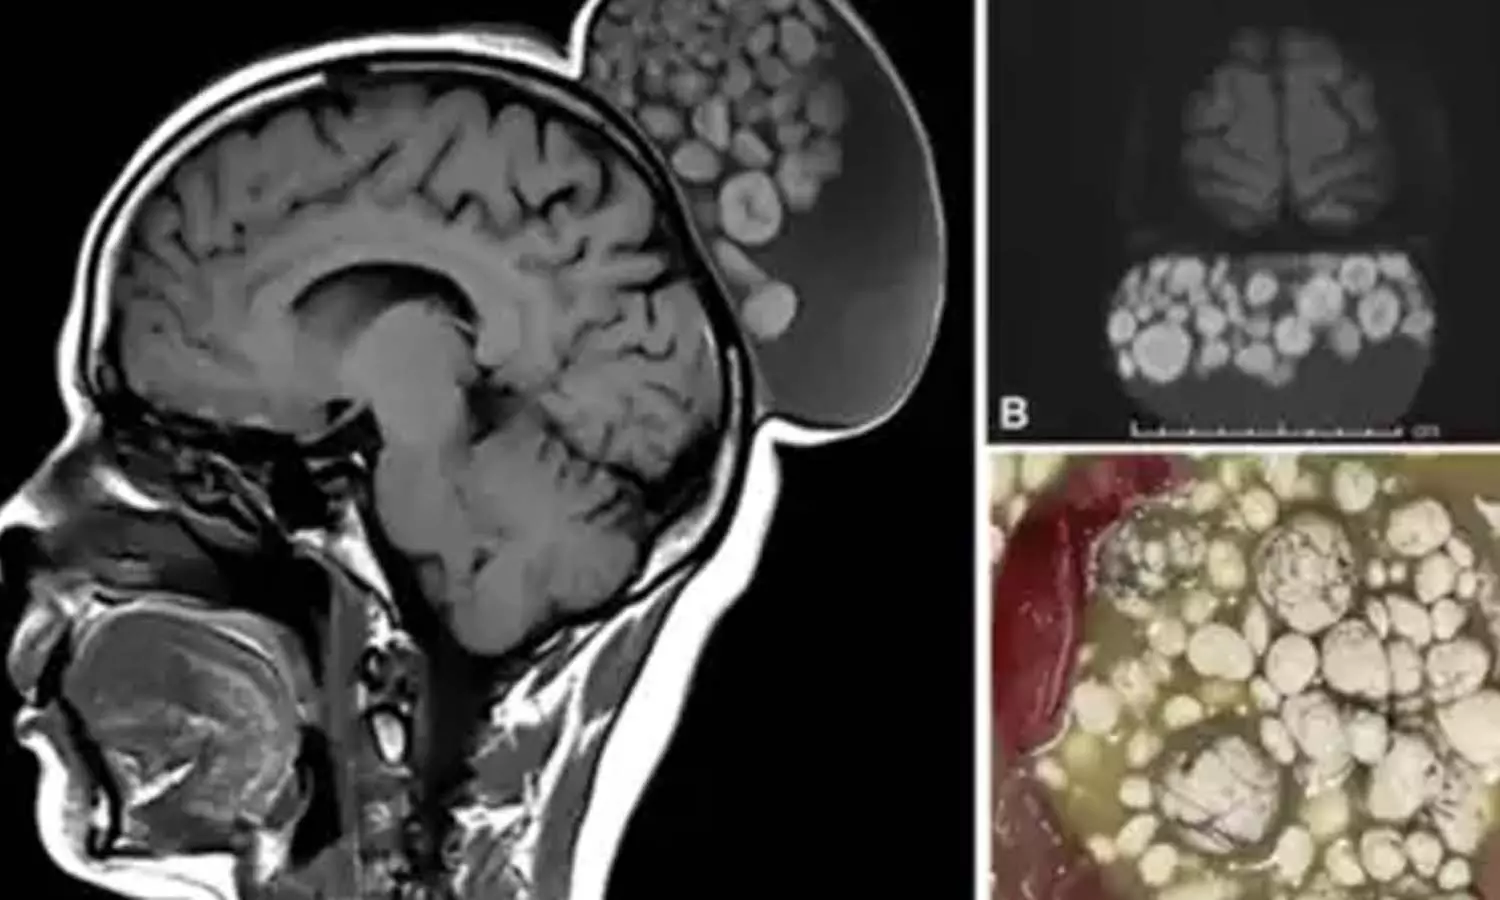

എംആർഐ സ്കാനിങ് നടത്തിയപ്പോഴാണ് 52കാരിയുടെ തലയോട്ടിയിൽ അസാധാരണമായ ഒരു കാര്യം കണ്ടെത്തിയത്. തടിച്ചുരുണ്ട മാർബിൾ കഷ്ണങ്ങൾ പോലെ ചിലത് തലയോട്ടിയിൽ വളരുന്നുണ്ടായിരുന്നു. കുട്ടിക്കാലം മുതൽ തന്നെ ഇവരുടെ തലയോട്ടിയിൽ ഈ അവസ്ഥ റൂളിപ്പെടുന്നുണ്ടായിരുന്നു എന്ന് ഡോക്ടർമാർ പറയുന്നു. അടുത്തിടെയാണ് ശ്രീ സത്യസായി ഇൻസ്റ്റിറ്റ്യൂട്ട് ഓഫ് ഹയർ മെഡിക്കൽ സയൻസസിലെ ഡോക്ടർമാർ 52കാരിയുടെ തലയോട്ടിയിൽ നിന്ന് ഇവ നീക്കം ചെയ്തത്.

കുട്ടിക്കാലം മുതൽ തന്നെ ഇവരുടെ തലയോട്ടിയിൽ ഒരു നീർവീക്കം ഉണ്ടായിരുന്നു. ഒരു വലിയ സിസ്റ്റിൽ പൊങ്ങിക്കിടക്കുന്ന വിവിധ വലുപ്പത്തിലുള്ള ഒന്നിലധികം നോഡ്യൂളുകൾ ആണെന്ന് സ്കാനിങ്ങിൽ കണ്ടെത്തി. മാർബിൾ കഷ്ണങ്ങളുടെ രൂപമായിരുന്നു ഇവയ്ക്കെന്ന് ഡോക്ടർമാർ പറയുന്നു. പാരീറ്റോ-ആക്സിപിറ്റൽ മേഖലയിൽ 15 × 10 × 12-സെ.മീ വലിപ്പമായിരുന്നു ഇവയ്ക്ക്.

എംആർഐ സ്കാനിൽ തലയോട്ടിയിലെ സബ്ഗലിയൽ തലത്തിൽ ഒരു മുറിവ് കാണപ്പെട്ടിരുന്നു. സിസ്റ്റിൽ പൊങ്ങിക്കിടക്കുന്ന വിവിധ വലുപ്പത്തിലുള്ള ഒന്നിലധികം നോഡ്യൂളുകൾ അടങ്ങിയിരുന്നു. ശസ്ത്രക്രിയക്ക് ശേഷം കട്ടിയുള്ള ഉരുളകൾ, ഒന്നിലധികം മുടിയിഴകൾ എന്നിവയും സിസ്റ്റിൽ നിന്ന് നീക്കം ചെയ്തു. ശസ്ത്രക്രിയക്ക് ശേഷം പിന്നീട് ഇവ വളർന്നിട്ടില്ലെന്ന് ഡോക്ടർമാർ പറയുന്നു.

കെരാറ്റിൻ, കൊഴുപ്പ്, സെബാസിയസ് മെറ്റീരിയൽ, ഫൈബ്രിൻ, മുടി എന്നിവയുടെ ഗോളാകൃതിയിലുള്ള അഗ്രഗേറ്റുകൾ സിസ്റ്റിന്റെ ദ്രാവക മാട്രിക്സിനുള്ളിൽ പൊങ്ങിക്കിടക്കുന്നതിനാലാണ് മാർബിൾ പോലെയുള്ള രൂപമുള്ളതെന്നാണ് റിപ്പോർട്ട്. ഇതൊരു അസാധാരണ സംഭവമാണെന്നും ഡോക്ടർമാർ പറയുന്നു.